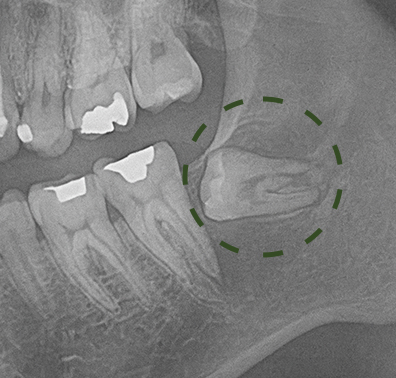

- 함치성 낭종 (Dentigerous Cyst)

- 잇몸 뼈 속 매복된 치아 주변에 생기는 낭성 병소

- 사랑니·유치·맹출하지 않은 치아에 발생

- 초기에는 증상이 없지만 방치 시 턱뼈 흡수, 주변 치아 이동 유발

- 조기 발견 시 국소적 수술로 완치 가능

- → 정기 CT 촬영으로 무증상 낭종 조기 발견 가능